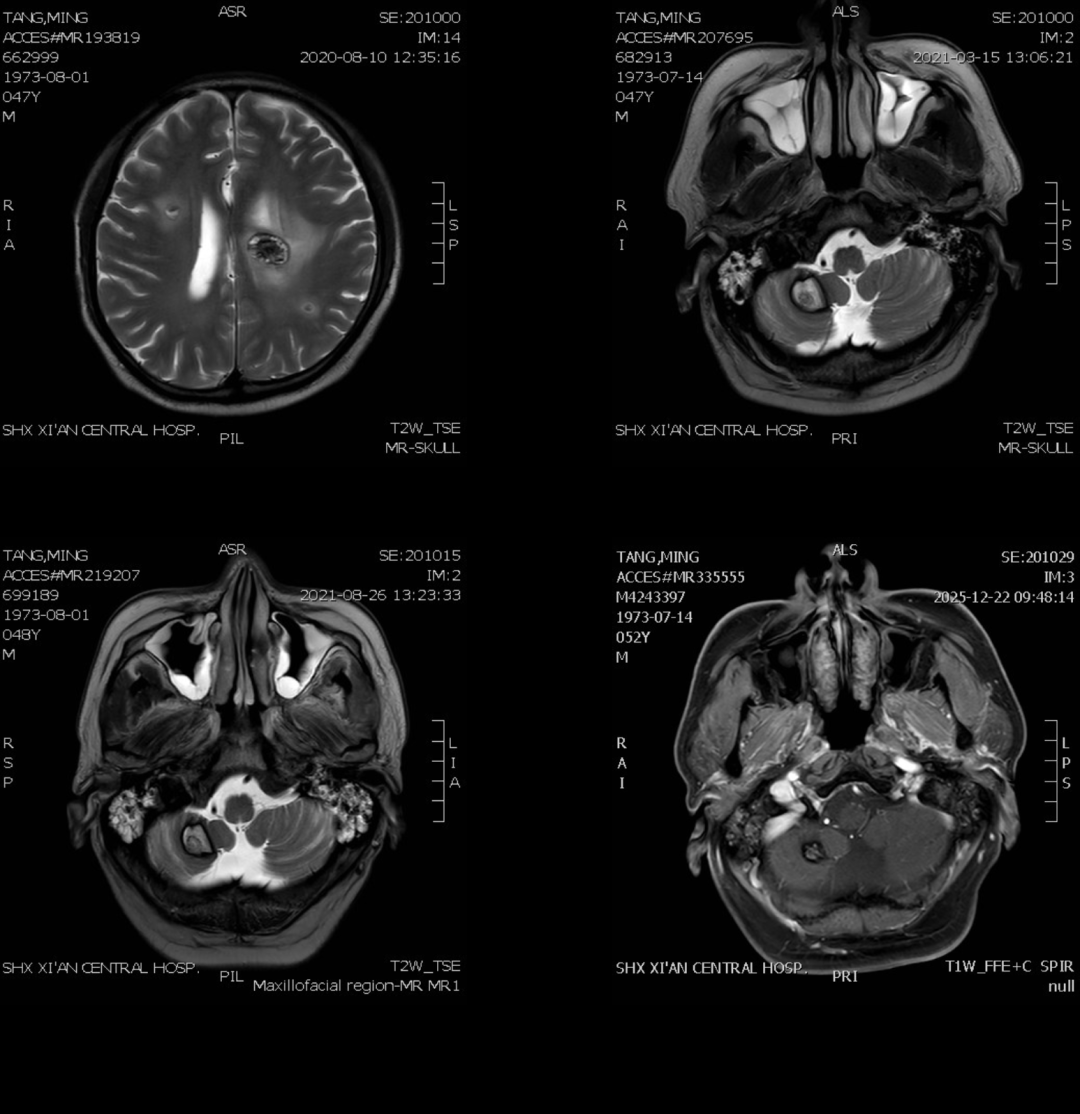

在接受靶向治疗后,患者规律随访复查。最新头颅磁共振结果显示,多发脑转移灶较前稳定,未见明显进展,提示颅内病灶得到持续有效控制。

(A图:2020.08.10头颅核磁复查;B图:2021.03.15头颅核磁复查;C图:2021.08.26头颅核磁复查;D图:2025.12.22头颅核磁复查)